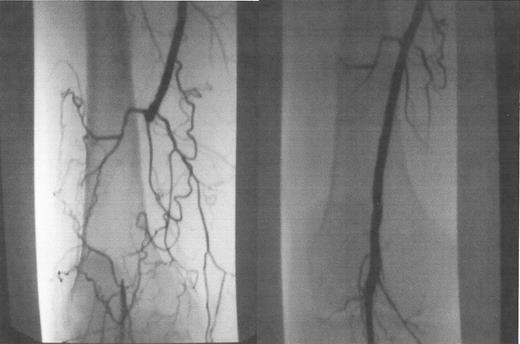

Laser-assisted balloon angioplasty is an endovascular technique that allows recanalization of long segment arterial occlusions that are too long to be successfully crossed with a guidewire and conventional techniques alone. Most short segment arterial occlusions can be crossed using standard guidewires with hydrophilic coatings that enable the wire to be “slipped” through an obstructed area. In some long segment lesions, however, this is not possible. The excimer laser device (Spectranetics, Colorado Springs, CO), on the other hand, is advanced in small increments along with the guidewire, while the laser energy recanalizes the occluded arterial segment. Once the diseased segment is crossed, a standard guidewire is placed through the area and it is treated with balloon angioplasty as with other arterial stenotic lesions (Figure 6 ). These devices come in a range of diameters (0.9–2.5 mm) and can be used for coronary and peripheral arterial lesions.

Occluded popliteal artery, before (A) and after (B) laser-assisted balloon angioplasty.